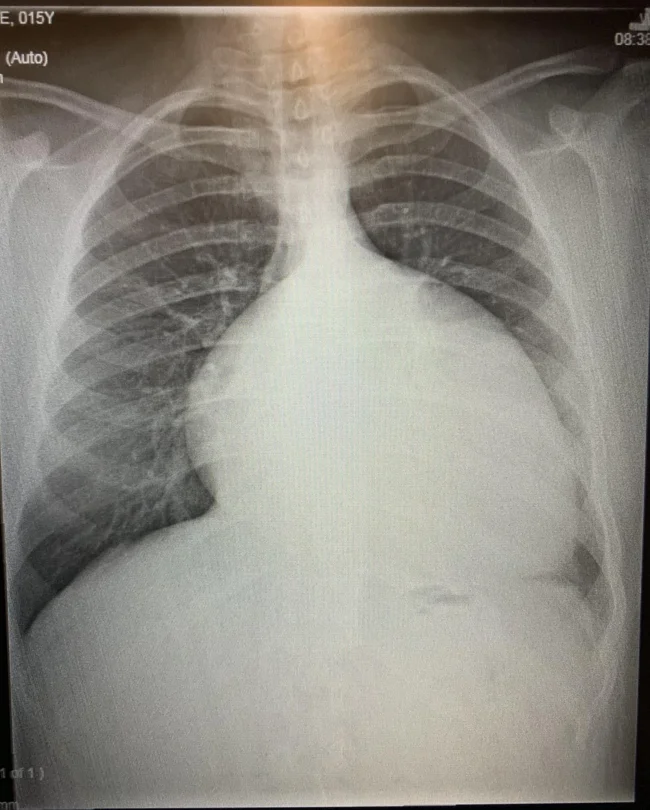

10. «Моё увеличенное сердце в 15 лет (2012 год) до операций»